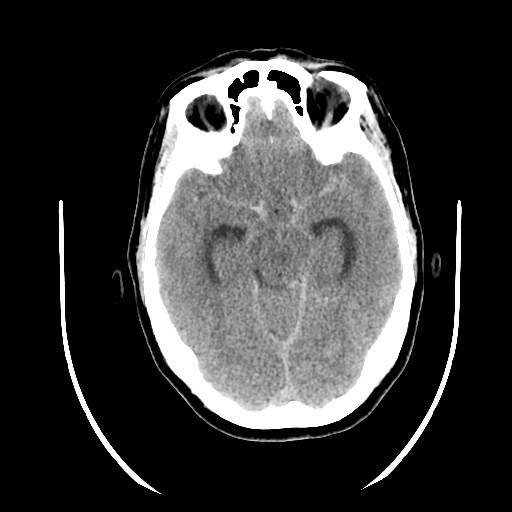

Grado 2- Capas difusas o verticales (fisura interhemisférica, cisterna insular,cisterna ambiens) < 1 mm de grosor.